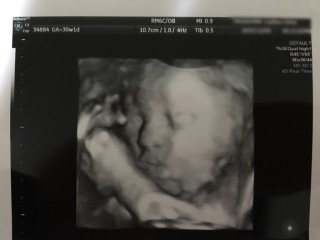

エコーは横顔の写真だそうです。頭もちゃんと

下にあり安心しました。